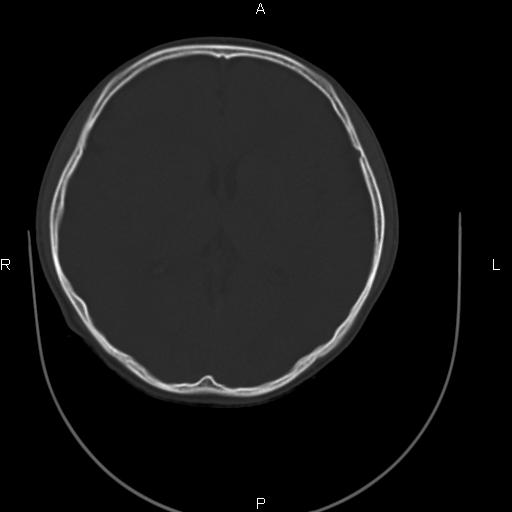

标题: CT27115:大家看一看,这孩子的颅骨表现? [打印本页]

标题: CT27115:大家看一看,这孩子的颅骨表现?

两名中学生打架,脑质内未见异常,未上传。

颅骨骨质未见异常。

颅骨未见骨折征象。

两例——颅骨结构正常,未见明显骨折征象。

感觉第2个颅缝密度高,额顶部板障有点厚,正常变异?地中海贫血?

未见异常